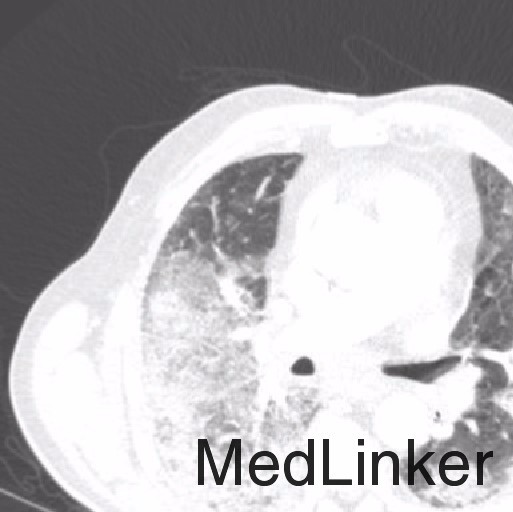

入院前5-6周胸部X线示双侧肺片団影(图1),怀疑为社区获得性肺炎,给予阿奇霉素和莫西沙星,症状无明显改善。入院后体检发现患者有中度呼吸窘迫,血压171/88 mmHg,血氧饱和度86%。查体:患者有双侧哮鸣音及啰音,余未查见特殊。白细胞计数正常,胸部X线提示右下肺和左肺中央显著地恶化(图2)。胸部CT提示弥漫性肺病变,右侧少量胸腔积液,胸内,颈下淋巴结肿大(图3)。